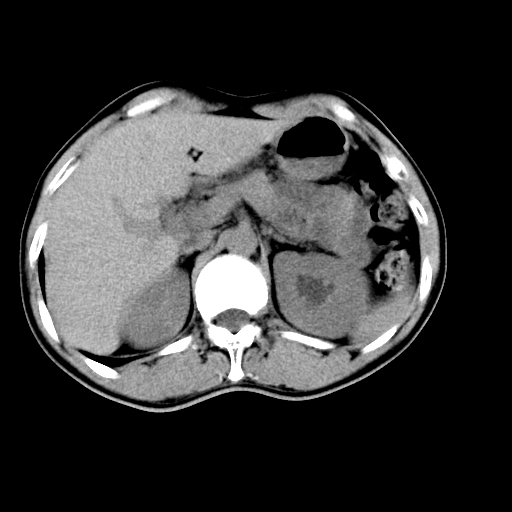

男,47岁,左输尿管结石碎石治疗后10余日。彩超示:左输尿管下段狭窄、输尿管积水。请各位讨论一下左输尿管下段结石还是静脉石?

象是第二狭窄处结石伴以上输尿管、肾盂轻度积水。

输尿管结石伴以上输尿管、肾盂轻度积水。

两侧髂总动脉壁斑状及点状钙化.左侧输尿管行经与左髂总动脉相交后见高密度影,且下段输尿管管腔未见扩张,应该要考虑结石伴以上输尿管及肾盂积水.但右侧结节状高密度影,也应该是结石吧!那以上输尿管未见扩张呢!因此静脉结石可能性也较大.请问楼主碎石前左侧输尿管结石位置.

虽左侧有轻度肾盂积水但不支持结石。1结石边周应该有软组织包绕呈晕征。2钙化点前面见输尿管影也不支持是结石。3彩超没提结石。建议超生复查。

输尿管先位于腹部,后进入盆腔,最后斜穿膀胱壁开口于膀胱,因此,临床上常将输尿管分为腹段、盆段和壁内段。第1个狭窄:在肾盂与输尿管移行处。第2个狭窄:在跨过髂血管处。第3个狭窄:在穿过膀胱壁处。这些狭窄是结石容易滞留的部位。